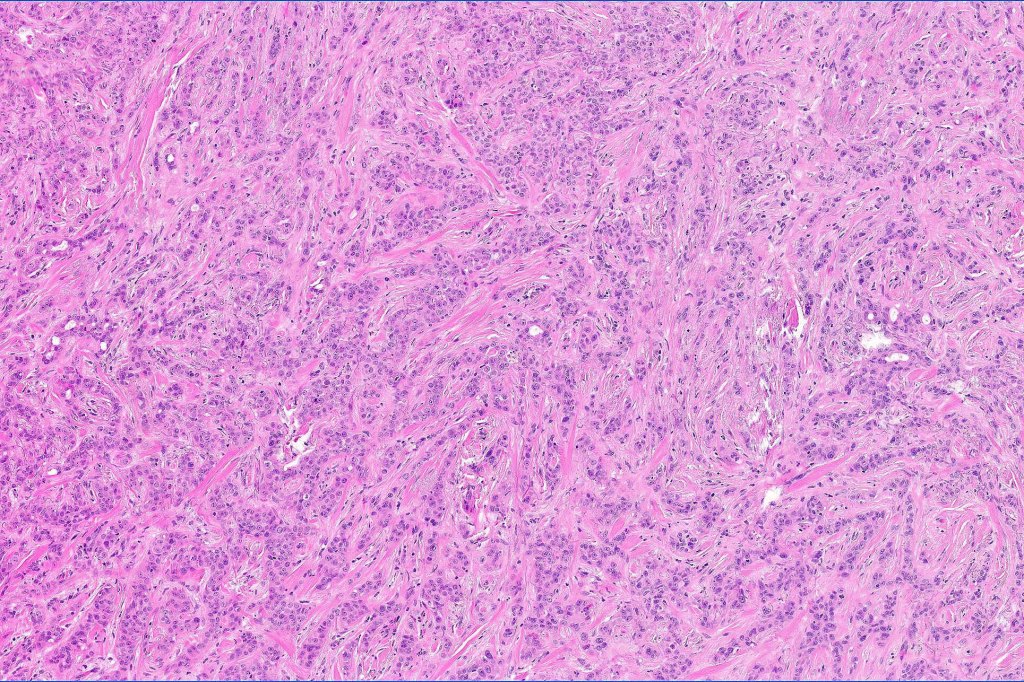

•Widely infiltrating biphasic tumor

•Often extends to the subcutaneous fat

•Perineural infiltration is commonly seen

•Microcystic adnexal carcinoma is sometimes confused with syringoid eccrine carcinoma. The former shows superficial keratocysts in the absence of SCC and in the deeper reaches, the epithelium is well differentiated & shows intracytoplasmic lumina and occasional well-formed ducts embedded in a dense fibrous stroma. Glands are not a feature